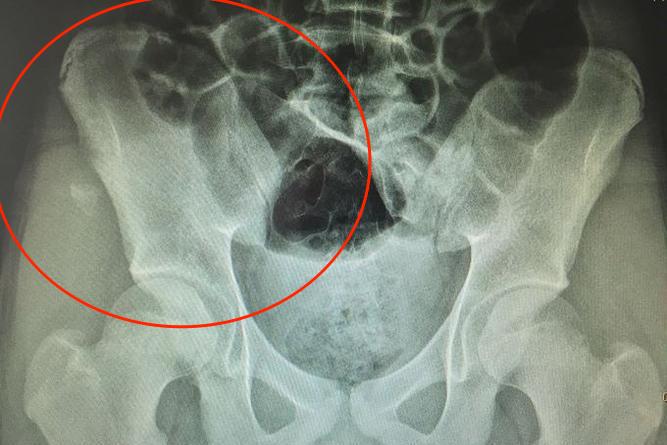

骨盆边缘部撕脱性骨折

好发于青少年,其病史中常有做某个动作时,突然发生骨盆区剧痛的过程。临床检查时,撕脱性骨折处有肿胀、触痛,髋关节活动受限,骨折片附着肌肉的主动和被动运动均会产生疼痛,骨折片可见不同程度分离移位。